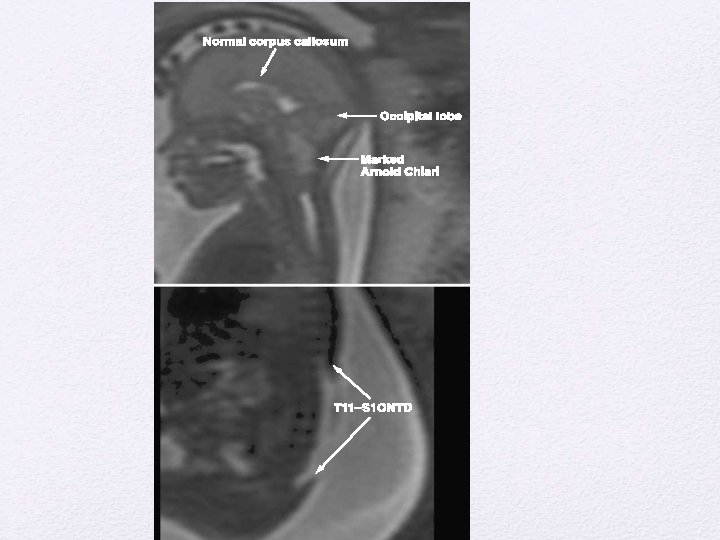

Spinal Dysraphism • Spinal dysraphism refers to a spectrum of disorders in which there is defective midline closure of neural, bony, or other mesenchymal tissues. • The “open” dysraphic states include myelocele, myelomeningocele, hydromyelia, Chiari II malformations, hemimyelocele, and myeloschisis. • The closed dysraphic states include entities such as dermal sinus, lipomyelomeningocele, tight filum terminale, meningocele, myelocystocele, diastemato- myelia, neurenteric cyst, slit notochord, and developmental tumors such as spinal lipomas

Myelomeningoceles • Disorder resulting from defective primary neurulation • 98% of all Spinal dysraphism • Incidence • 0. 4 per 1000 live births • Racially variable • 85% caudal thoraco lumbar spine, 10 % in the torax and the rest cervical • 80 -90 % associated with hydrocephalus and Chiari • Trisomy 13 and trisomy 18

Associated defects • Brain stem defect includes • Medullary kinking, tectal beaking, and intrinsic nuclei abnormalities • Supratentorial abnormalities include • partial or complete dysgenesis of the corpus callosum, • polymicrogyria, a large massa intermedia, and gray matter heterotopia. • Mesodermal development of the skull • • small posterior fossa, short clivus, low-lying tentorium and torcular Herophili, wide incisura, and enlarged foramen magnum. craniolacunia (scalloping of the skull bones)